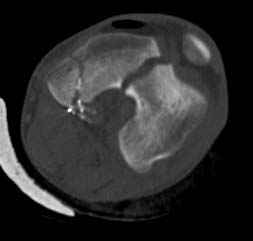

По Густило и Андерсену все high-energy переломы являются III не зависимо от степени повреждения мягких тканей. Plating такого перелома на второй день кажется немного рискованным хотя "победителей не судят". Судя по КТ, медиальный мыщелок стабильный, насколько необходимо было его фиксировать?

Идеальная репозиция?! -На снимочке A-P проeкции видна "зазубрина" по суставной поверхности, латеральный снимок - тоже не идеально.